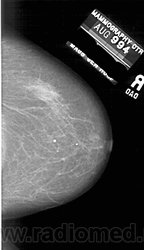

Со старением железистая ткань постепенно исчезает: прозрачность жировой ткани становится преобладающей с несколькими каркасами, связанными с опорными волокнистыми структурами.

Жирная (не плотная) грудь

Умеренно плотная грудь

Плотная грудь

Маммограммы представляют собой изображения структур, проецируемых на плоскость: плотная грудная маммограмма, следовательно, состоит из многих других структур, которые необходимо проанализировать, чем более жирная, пустая грудь. По этой причине диагностировать рак молочной железы труднее для моложе, чем для пожилых женщин.

Нажмите на миниатюрные картинки, чтобы получить увеличенный размер.